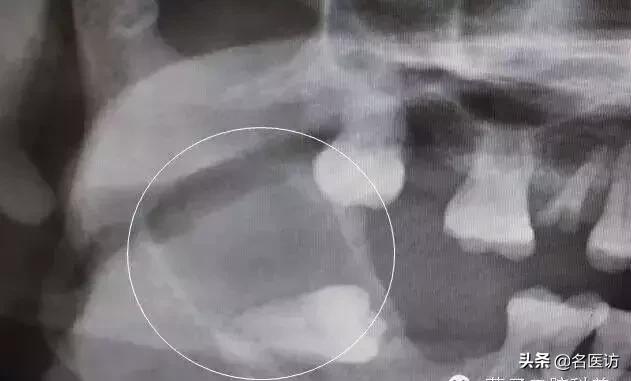

智齿引起下颌骨大面积囊肿

特别提醒:如果有需要拔除的智齿,一定是“宜早不宜晚”,也就是趁着年轻赶紧拔除。因为和年纪大的人相比,年轻人智齿的拔除难度小,术后恢复快,并发症少。如果要拔智齿,在 18-20 岁左右最好。